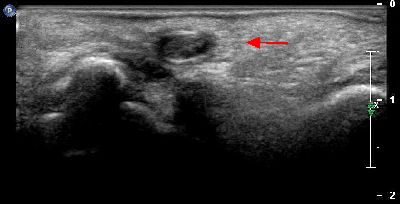

Pannicolo fibrotico intrarticolare

(caso del paziente A.C.)